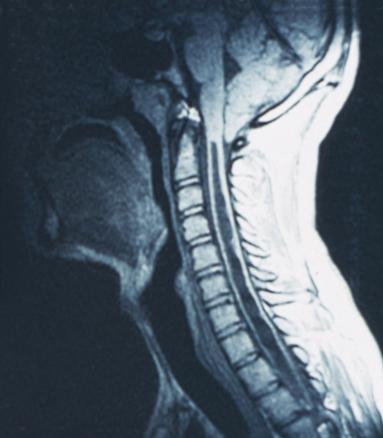

Il s'agit d'une syringomyélie.Le diagnostic de syndrome médullaire reste avant tout clinique. Le diagnostic étiologique de syndrome médullaire a été nettement amélioré par la résonance magnétique nucléaire qui permet rapidement d'éliminer une cause compressive et d'orienter l'exploration étiologique. Une fois éliminée une cause compressive, la ponction lombaire garde toute sa place pour compléter l'approche diagnostique. Cela doit aboutir le plus rapidement possible à un traitement, curatif dans certains cas, symptomatique dans les autres cas, notamment en cas de syringomyélie. La syringomyélie est une cavité centromédullaire d'origine malformative ou post-traumatique. La symptomatologie est principalement sensitive, thermo-algique, suspendue, par lésion des fibres spinothalamiques centromédullaires. Une atteinte motrice est plus inconstante, témoignant d'une extension de la cavité vers la corne antérieure médullaire, et se manifeste par une amyotrophie et une abolition des réflexes ostéotendineux dans le territoire concerné.Pour en savoir plus :- de Seze J. Affections non traumatiques de la moelle épinière. Rev Prat 2001;51(11):1215-8.- Fleury MC, Tranchant C. Compression médullaire non traumatique et syndrome de la queue de cheval. Rev Prat 2006;56(4):419-23.- Caire F, Moreau JJ. Compression médullaire non traumatique. Rev Prat 2010;60(8):1144-8.